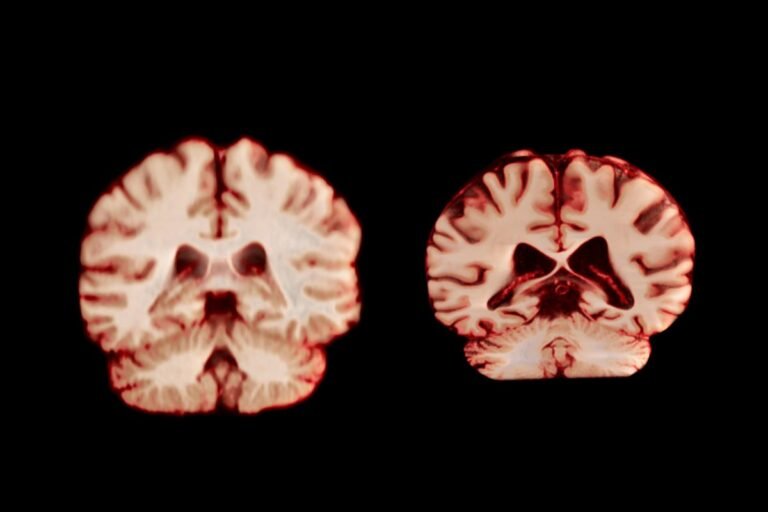

A healthy brain (left) and a brain affected by Alzheimer’s disease.

TheVisualMD/Science Source